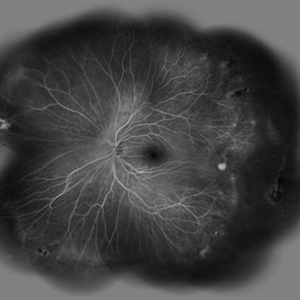

Behcet's Disease Behcet's DiseaseMar 13 2013 by Hamid Ahmadieh, MD Early phase FA of the right eye of a 23-year-old man with retinal vasculitis and branch retinal vein occlusion (BRVO) due to Behcet's disease . Photographer: Solmaz Shahmohammad, Negah Eye Center, Tehran Imaging device: Heidelberg Spectralis Condition/keywords: branch retinal vein occlusion (BRVO), retinal vasculitis

Behcet's Disease Behcet's DiseaseMar 13 2013 by Hamid Ahmadieh, MD Mid phase FA of the right eye of a 23-year-old man with retinal vasculitis and branch retinal vein occlusion (BRVO) due to Behcet's disease . Photographer: Solmaz Shahmohammad, Negah Eye Center, Tehran Imaging device: Heidelberg Spectralis Condition/keywords: branch retinal vein occlusion (BRVO), retinal vasculitis